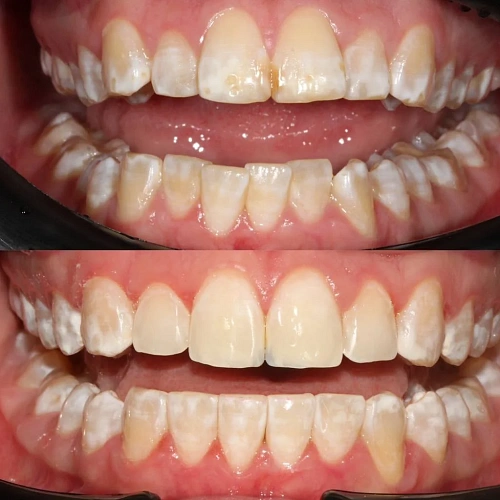

Лечение неправильного прикуса зубов на элайнерах Click Aligners за 23 месяца

Нарушение соотношения челюстей и неправильное положение зубов — зубные ряды смыкались некорректно, зубы стояли со смещением.

Прозрачные элайнеры Click на обе челюсти. Выровнять зубы и нормализовать смыкание. Основной набор — 20 кап. Срок — около 1 года.

Лечение заняло 23 месяца (октябрь 2023 — сентябрь 2025). Понадобился один дополнительный набор из 10 кап — итого 30 кап.

Зубы выровнены, смыкание нормализовано. Установлены несъёмные ретейнеры на обе челюсти, сняты сканы для ретенционных кап.

Проблема: Пациентку не устраивало положение зубов и то, как смыкаются челюсти. Зубы стояли неровно, ряды сходились неправильно.

Решение: Поставили прозрачные элайнеры Click — начали с компактного набора из 20 кап. Основной комплект сделал основной объем работы, но для финальной доводки понадобился дополнительный набор из 10 кап. Итого 30 кап за 23 месяца. Результат — зубы на месте, смыкание в норме. Зафиксировали ретейнеры на обе челюсти, сняли сканы для ретенционных кап.